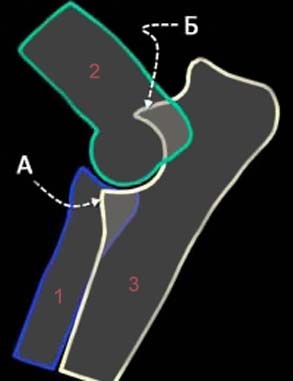

A - koronoid

B - hamulus

1 - sugara

2 - felkarcsont

3 - ulna

Hámlasztó osteochondritis felhívja a helyi túlterhelés koronoid, ami deformáció porcos rétegek korlátozása közös mozgás és szétválását a csont töredékek. Ugyanez történik, ha a könyökízület osteoarthritis, ami előfordulhat fiatal állat miatt mechanikus vagy biológiai hatások növekvő szervezet (trauma, a kalcium és a foszfor a kiegyensúlyozatlan táplálkozás). Például, ha a metaphysis sérült miatt trauma vagy tömörített, majd roncsoltuk szállítási tápanyagok a mátrix réteg a csont. Ez ahhoz vezet, hogy lehetetlenné válik a normál csont növekedését, az ízületet alkotó és lassítja a kialakulását porcos rétegeket. Ennek eredményeként a csukló ízületi felszínek válik diskongruentnym.

A fragmentáció koronoid az eredménye kialakulhatna egy „lépés” az a hely, az alkar csontjai ízületek miatt lag a fejlesztés a sugár. A másik oka a kár a koronoid társított forgása a radiális csont, akkor fordul elő, amikor az egyén anatómiai jellemzői ín-izomrendszer bicepsz. folyamat túlterhelés is előfordulhat, ha egy kóros formája a cavitas glenoidalis, amelyben a közös egység kissé eltolódik normál helyzetébe, és hozzon létre nyomást a csontra.

Okai szigetelés hooklike folyamat hasonló az oka a töredezettség koronoid fent leírt: a formáció a „lépés” az a hely, az artikuláció, az alkar csontjai, de ez annak köszönhető, hogy a lemaradás a növekedés hosszabb ulna - eredményeként a közös egység felfelé mozog, torlódást okozó hooklike folyamat . Szétválasztása a folyamat továbbra is bekövetkezhetnek késleltetett csontképződés metafízisen közte és a könyök nyúlvány halom - kis terhelés a sérült rész kinövést.